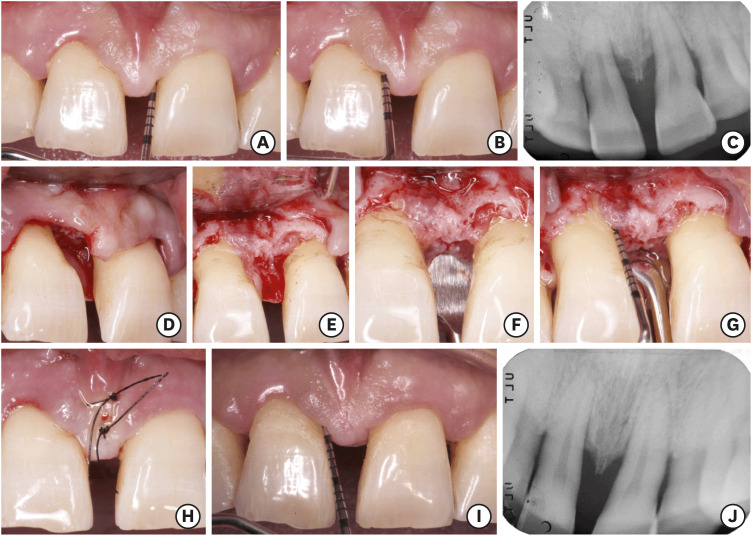

目的:本研究的目的是评估牙周通道瓣手术中牙周肉芽组织保存(PGTP)的临床效果。方法:连续招募20例(III-IV期牙周炎患者),42个深度牙周袋经非手术治疗后仍未消退。采用PGTP改良牙周皮瓣手术。9个月时评估临床牙周参数。评价了肉芽组织宽度(GTw)保存量的差异,并分析了吸烟对肉芽组织宽度的影响。结果:97.6%的近端缺损GTw >1 mm, 71.4%的缺损肉芽组织延伸至骨峰以上。9个月时,探查袋深度减少(4.33±1.43 mm)和临床附着增加(CAG;4.10±1.75 mm)差异有统计学意义(PPP0 mm)。吸烟者的临床结果明显更差。结论:PGTP在修复牙周通道瓣手术中具有良好的修复作用,保留了受损组织。结果表明,保留牙周肉芽组织是牙周病手术治疗中一种有效且保守的方法。

Purpose: The aim of this study was to evaluate the clinical outcomes of periodontal granulation tissue preservation (PGTP) in access flap periodontal surgery.

Methods: Twenty patients (stage III-IV periodontitis) with 42 deep periodontal pockets that did not resolve after non-surgical treatment were consecutively recruited. Access flap periodontal surgery was modified using PGTP. The clinical periodontal parameters were evaluated at 9 months. The differences in the amount of granulation tissue width (GTw) preserved were evaluated and the influence of smoking was analyzed.

Results: GTw >1 mm was observed in 97.6% of interproximal defects, and the granulation tissue extended above the bone peak in 71.4% of defects. At 9 months, probing pocket depth reduction (4.33±1.43 mm) and clinical attachment gain (CAG; 4.10±1.75 mm) were statistically significant (P<0.001). The residual probing depth was 3.2±0.89 mm. When GTw extended above the interproximal bone peak (i.e., the interproximal supra-alveolar granulation tissue thickness [iSUPRA-GT] was greater than 0 mm), a significant CAG was recorded in the supra-alveolar component (1.67±1.32 mm, P<0.001). Interproximal gingival recession (iGR) was significant (P<0.05) only in smokers, with a reduction in the interdental papillary tissue height of 0.93±0.76 mm. In non-smokers, there was no increase in the iGR when the iSUPRA-GT was >0 mm. The clinical results in smokers were significantly worse.

Conclusions: PGTP was used to modify access flap periodontal surgery by preserving affected tissues with the potential for recovery. The results show that preserving periodontal granulation tissue is an effective and conservative procedure in the surgical treatment of periodontal disease.